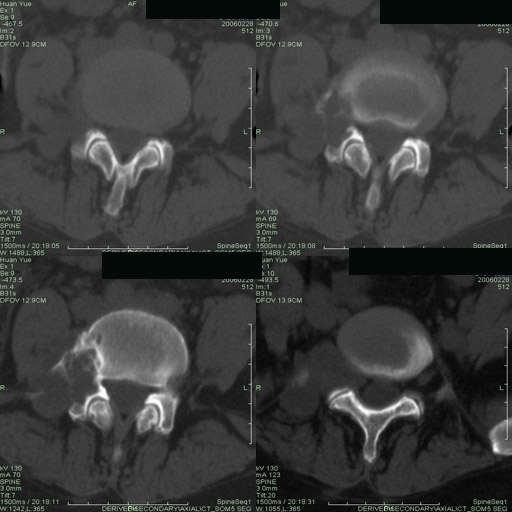

以下是引用听蝉观竹在2006-3-5 23:09:00的发言:[br]这个病例不考虑神经源性肿瘤,首先考虑转移瘤,因为它不是受压造成骨质吸收,而是从骨骼的松质部分由中心向外破坏的,不仅仅是横突,而且同侧椎弓根也破坏了。[br]神经源性肿瘤-----受压造成骨质吸收。[br]转移性肿瘤------从骨骼的松质部分由中心向外溶骨破坏,多见椎弓根也破坏。

以下是引用徐大夫在2006-3-5 20:32:00的发言:[br]骨缺损区边缘有硬化,结合部位,考虑神经源性良性肿瘤。